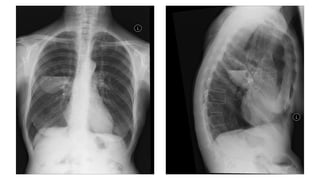

Pneumonias Can Be Subtle On The PA View Alone.

51 Year-Old With

Cough & Fever.

Retrocardiac LLL Pneumonia On The Lateral View